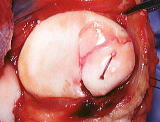

大腿骨外側顆に 大きな軟骨欠損

外側顆に20x15mm 大の軟骨欠損

遊離軟骨片を 吸収性ピンで固定